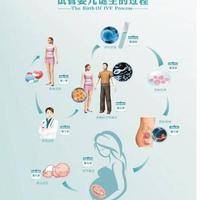

随着科学技术的相继进步,试管婴儿技术也在陆续发展。美国凭借先进的医疗技术和丰富的临床经验,在试管婴儿范围处于较洼地位。三代试管婴儿中的PGS技术,更是为提高试管婴儿成功率和保障胎儿健康提供了有力支持。下面,我们详细剖析美国三代试管婴儿的成功率以及PGS技术筛选健康胚胎的过程。

筛选过程:起首,在试管婴儿治疗过程当中,通过促排卵取得多个卵子,与精子结合组成受孕卵并培养至囊胚阶段。然后,医生会从囊胚从中获取出数个细胞个体进行检测。这一过程须要在专业的实验室中由有经验的医生操作,以保障不影响胚胎的发育。接下来,实验室利用前沿的基因检测技术,如新一代测序技术(NGS)等,对拿出的细胞个体进行染色体解析。最后,根据检测结果,选择染色体正常的胚胎进行移植,这般可以大大降低早产和胎儿染色体异常的风险。

PGS技术的优势:PGS技术可以提高试管婴儿的成功率,因为移植健康的胚胎着床概率更高。同一时刻,它能够够减轻因染色体异样导致的小产、胎儿先天性畸形等情况,提高生育质量,让家庭能够具有健康的宝宝。